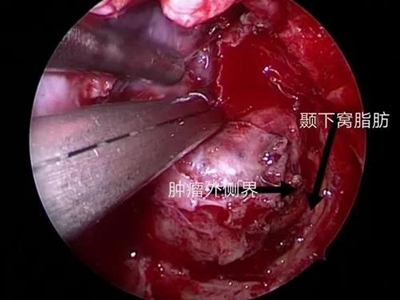

鼻咽纤维血管瘤又名“男性青春期出血性鼻咽血管纤维瘤”,是起源于鼻咽部的良性肿瘤,好发于14-25岁的男性青年,在鼻咽部的良性肿瘤中居首位。侵犯周围组织的能力较强,随瘤体的不断增大,易扩展到眼眶、鼻腔,甚至颅内,导致严重的并发症。

3、其他症状:肿瘤压迫咽鼓管,引起耳鸣、耳闭及听力下降。肿瘤侵入邻近结构则出现相应症状,如侵入眼眶,则出现眼球突出,视力下降;侵入翼腭窝引起面颊部隆起;侵入颅内压迫神经引起头痛及其他颅神经瘫痪。

鼻咽纤维血管瘤以手术切除为主要治疗方式。围手术期需要进行血管栓塞,术中控制低血压等。少数不能立即手术的患者,可酌用放射治疗、注射硬化剂、内服激素等治疗,等待手术时机。